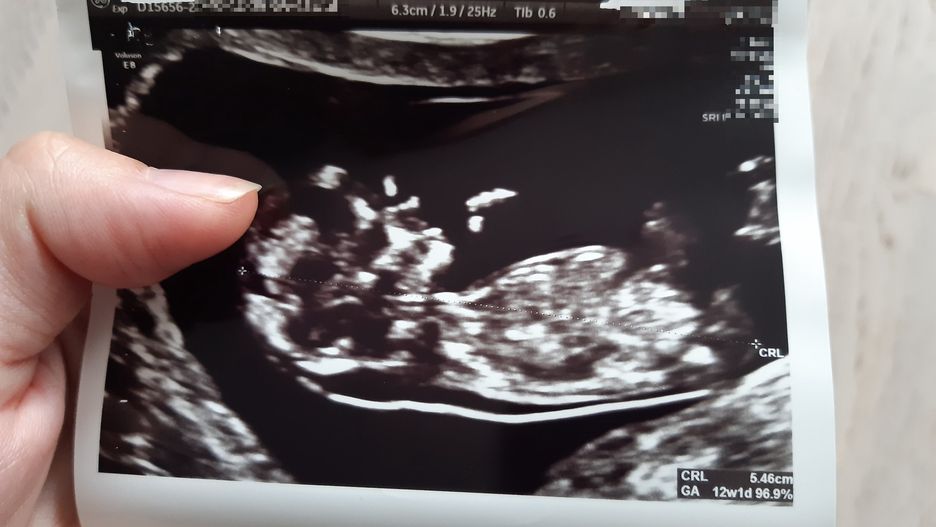

USG synka AnetyUSG synka Anety z widoczną zbyt dużą przeziernością karkową

Badanie USG w 12. tygodniu ciąży. Lekarz powiększa okolicę karku dziecka. Kilkanaście razy mierzy to samo miejsce. Milczy. – Coś nie tak? – pyta Aneta. – Sprawdzam dwunasty raz. Za duża ta przezierność. Nie mam dobrych informacji. Może być zespół Downa – mówi lekarz.

Na podstawie parametrów określonych w badaniu USG ginekolog wylicza prawdopodobieństwo wady u dziecka. Zespół Downa 1:10. Zespół Turnera 1:24. Zespół Pataua 1:36. – Przezierność karkowa sięga 4. Norma jest do 2,5. Zdrowe dziecko to byłaby kategoria "cud" – mówi lekarz i wypisuje skierowanie na amniopunkcję. To badanie, w czasie którego wbija się igłę w brzuch i pobiera płyn owodniowy, w którym zanurzone jest dziecko. Wynik w 100 proc. określa, czy dziecko ma wadę genetyczną.